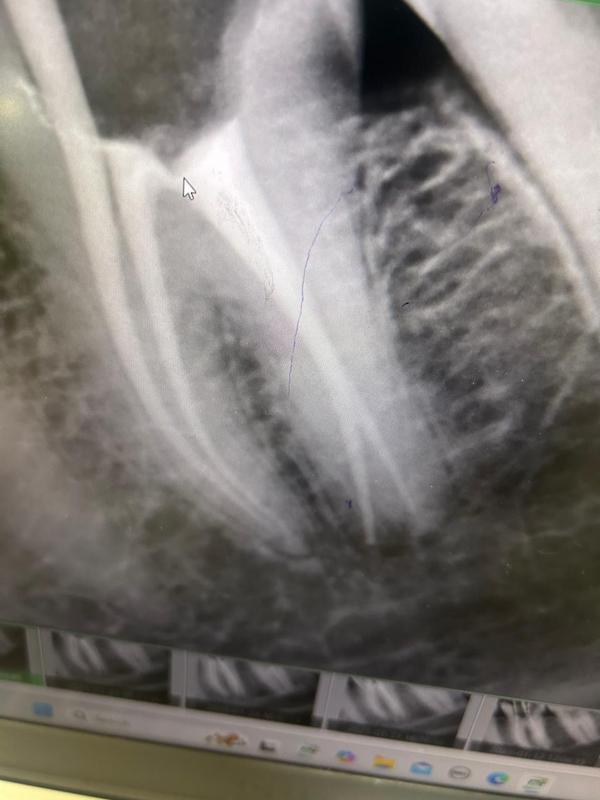

Dental implants are titanium posts surgically placed in the jawbone to replace the root of a missing tooth, providing a stable base for an artificial tooth, crown, bridge, or denture. They function, look, and feel like natural teeth, offer a long-lasting solution, and help prevent jawbone loss. The process involves surgically placing the implant, allowing time for it to fuse with the bone, and then attaching an abutment and artificial tooth